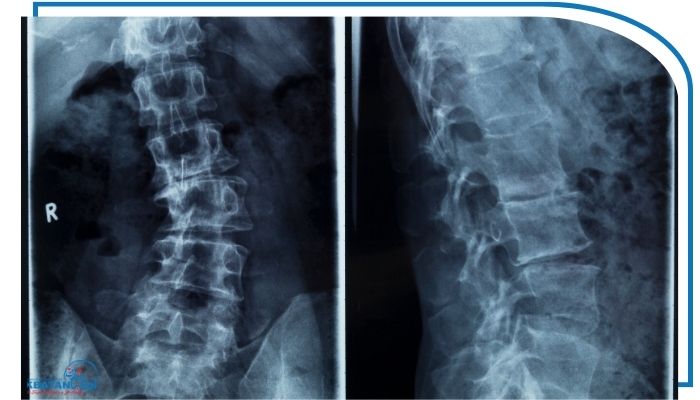

رادیوگرافی (X-ray)

رایج‌ترین روش تشخیص دقیق: نمای کامل از ستون فقرات ارائه می‌دهد.

زاویه Cobb: پزشک با اندازه‌گیری این زاویه بر اساس عکس رادیولوژی شدت اسکولیوز را تعیین می‌کند:

زیر ۱۰ درجه: طبیعی یا بسیار خفیف

۱۰ تا ۲۵ درجه: خفیف

۲۵ تا ۴۰ درجه: متوسط

بالای ۴۰ درجه: شدید